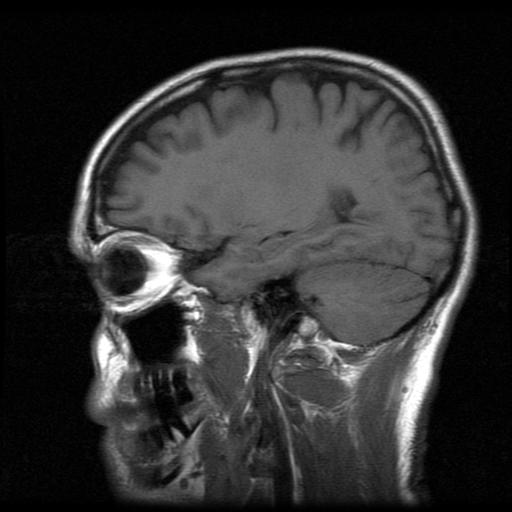

Often times, a difficult labor or delivery puts infants at risk for cerebral palsy. In fact, oxygen deprivation is one of the leading causes of cerebral palsy among children. When the child’s brain is deprived of oxygen due to complications such as breech birth, shoulder dystocia or cord entanglement, the baby may get asphyxiated. Brain damage caused in such a situation might lead to cerebral palsy. Any type of trauma or injury to the child’s brain during birth may result in cerebral palsy. Sometimes, when an obstetrician applies too much force while trying to get the baby out, cerebral palsy may occur. You may be able to obtain significant compensation for your child’s future care and treatment by filing a cerebral palsy lawsuit.